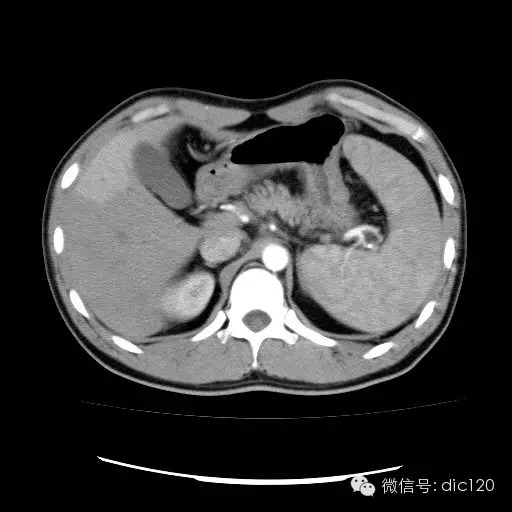

| 影像表现及分析: | 影像表现:动脉期扫描肝右叶紧贴边缘见一过性楔形高密度强化区,边界清,边缘平直,临近血管走形自然,门静脉期期恢复正常肝实质密度,延迟保持与肝实质密度一致。 |

| 疾病总结: | 正常肝脏的双重血供并非2个独立系统,两者之间有许多交通吻合,包括①肝窦间通路.②脉管间途径.③血管丛途径,即胆管周围血管丛途径.当肝脏发生血供障碍时,通过神经一体液因素的调节这些交通吻合支开放,双重供血发生血流量的变化甚至血流方向的改变.肝脏的这种”一过性”灌注异常在SCT表现为肝动脉期一过性肝实质强化(THPE).一过性肝实质强化差异是SCT增强扫描于肝动脉期表现的肝脏一过性灌注异常,大多数情况下它反映了局部肝脏双重血供的重新分布,即局部肝实质门静脉或肝静脉血流量减少,肝动脉血流量增多或为肝动脉门静脉分流或局部肝脏的变异或迷走血供所致。典型CT表现为肝动脉期一过性楔形或三角形高密度强化区,边缘平直,常位于肝脏边缘部位,其中血管走行正常,门静脉期恢复为正常肝实质密度。放射学医师应加强对一过性肝实质强化CT表现的认识。 |